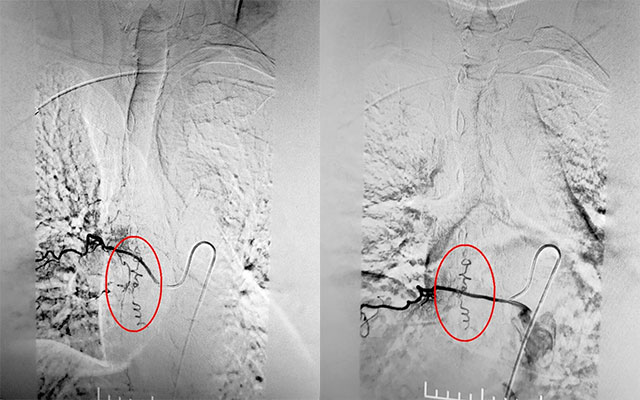

▲ DSA确诊硬脊膜动静脉瘘

为了定位病灶,3月16日下午1点,在复合手术室,张琪博士在刘春医生、周林华医生协助下通过股动脉穿刺术将造影剂推入各个脊髓间动脉。需要一条动脉一条动脉的试,并且脊髓间动脉复杂,需要非常细致的手法,十分考验医生的细心与耐心。经过两个多小时的连续造影,终于在T8右侧肋间动脉发现瘘口。“造影提示,该处瘘口由肋间动脉供血至硬脊膜静脉,脊髓引流静脉迂曲扩张明显。”张琪博士解释道。